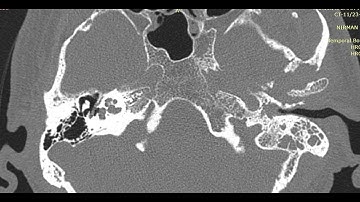

CT Temporal Bone Made Easy (Part 1) - Step by Step Approach